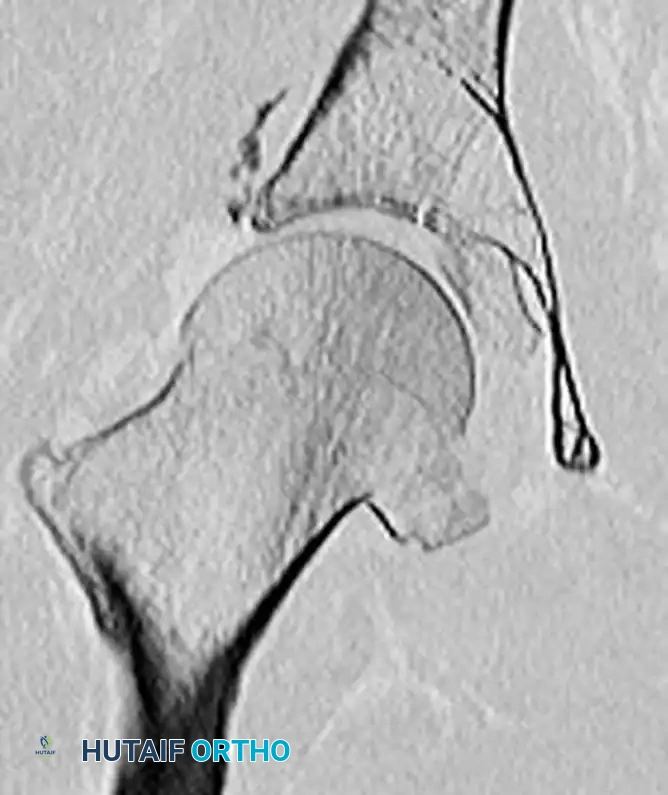

Figure 55-61A: Preoperative radiograph demonstrating a complex Pipkin IV fracture (posterior wall acetabular fracture with an associated femoral head fracture).

Figure 55-61B: Postoperative radiograph following surgical dislocation of the hip, open reduction and internal fixation of the posterior wall acetabular fracture, and débridement of the infrafoveal femoral head fracture.

Figure 55-61C: Postoperative axial CT scan confirming concentric reduction and hardware placement.

Figure 55-61D: Postoperative coronal CT scan demonstrating restoration of the articular congruity.